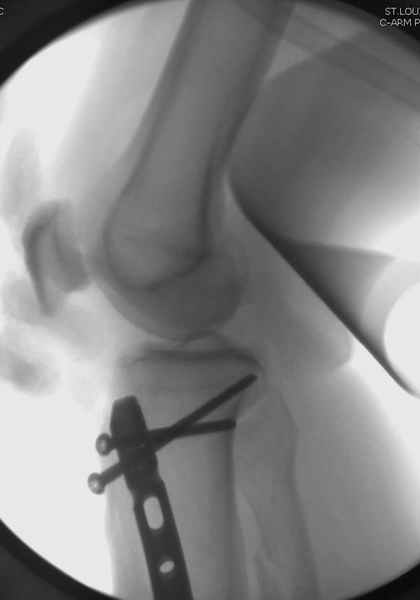

Здесь мы использовали новый Synthes Nail с дополнительными дырками, в проксимальной части 4: по две косых и поперечные (один стандартный а другой динамический), в дистальной части две поперечные, прямая и косая. Вес больного более 120 кг, нагрузку начнем через месяц.

При такий спирали задний край tibia может быть сломан - нет ли этого в данном случае? На всякий случай можно было ввести 1-2 винта 4,5 мм спереди назад мимо гвоздя. Хотя самый дистальный блокирующий винт, возможно, зацепил этот отломок. А какой тут диаметр гвоздя и locking винтов?

Если там и правда сломан задний край, то лучше с нагрузкой подождать, даже будь больной полегче.